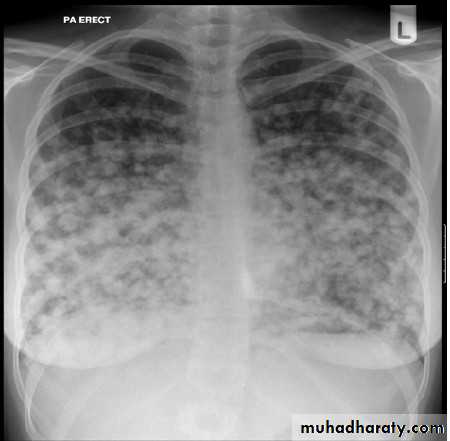

The chest x ray shows bilateral multiple nodules. Pulmonary nodules can be benign or malignant. Common benign causes include infectious granuloma, bronchial adenoma, and benign hamartoma. Malignant causes include primary lung cancer and metastases.